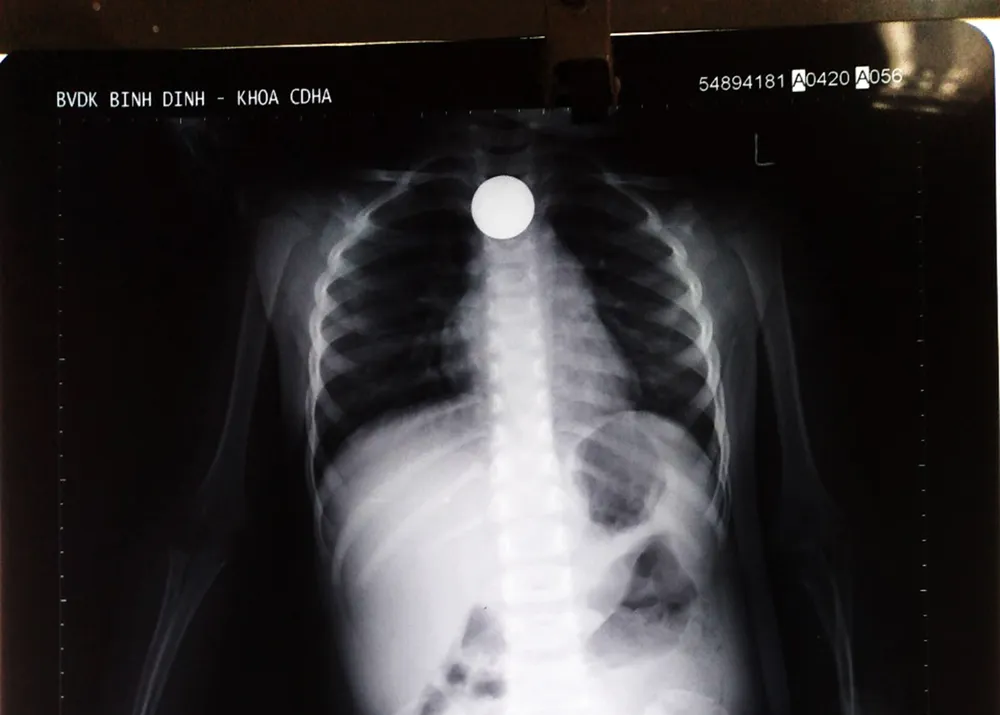

Bác sỹ CKII Võ Thành Nam Bình, Trưởng Khoa Nội tiêu hóa cho biết, ngay khi tiếp nhận bệnh nhân, ông đã chỉ đạo kíp trực tiến hành chụp phim, xác định đồng xu mắc ở vùng cuối thực quản cháu bé.

“Khoảng 11 giờ, chúng tôi tiến hành chuyển cháu qua khoa Chẩn đoán hình ảnh – Thăm dò chức năng để tiến hành phẫu thuật nội soi tiêu hóa lấy dị vật ra. 20 phút sau thì chúng tôi đã lấy thành công đồng xu ra khỏi thực quản cháu T.”, BS Nam Bình cho biết.